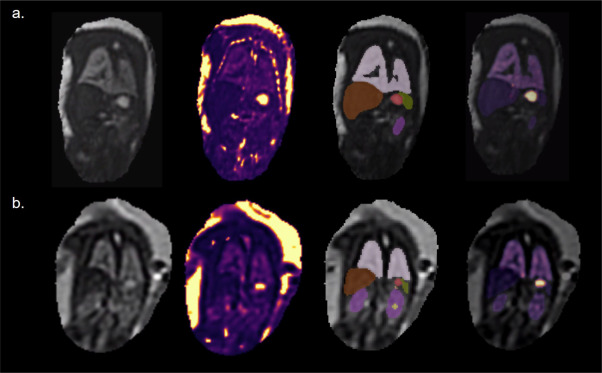

图6.从左到右:第二个回波的胎儿可变形切片到体素重建(dSVR)示例;T2*图dSVR(使用"地狱"色图显示,从深蓝色(0 ms)到亮黄色(1000 ms));多通道网络生成的标签图;叠加在第二个回波3D体积重建上的器官T2*图。上排:胎龄35.71周,下排:胎龄23.14周。